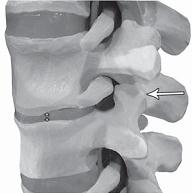

На МРТ № 4 наблюдается межпозвонковый диск в начальной стадии развития дегенеративно-дистрофического процесса.

На МРТ № 5 наблюдается межпозвонковый диск на более поздней стадии развития дегенеративно-дистрофического процесса.